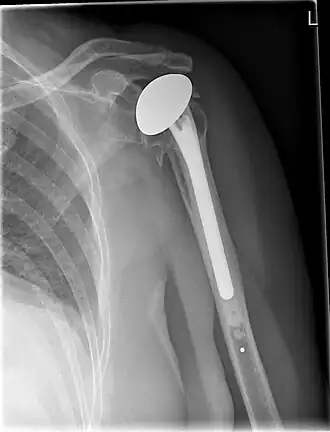

Een kunstgewricht is een kunstmatig gewricht dat dient ter vervanging van natuurlijke gewrichten, die door slijtage of ziekte niet meer functioneren.

Kunstgewrichten worden toegepast voor heupen, knieën, schouders,ellebogen enkels en polsen.

Kunstheupen zijn zeer succesvol, gevolgd door knieën, maar ook vervangende kunstschouders, -enkels en -polsen winnen terrein. In de rug worden ook versleten of beschadigde (tussen)wervelschijven meer en meer vervangen, maar door de vele zenuwbanen en dergelijke is dat niet zonder risico.